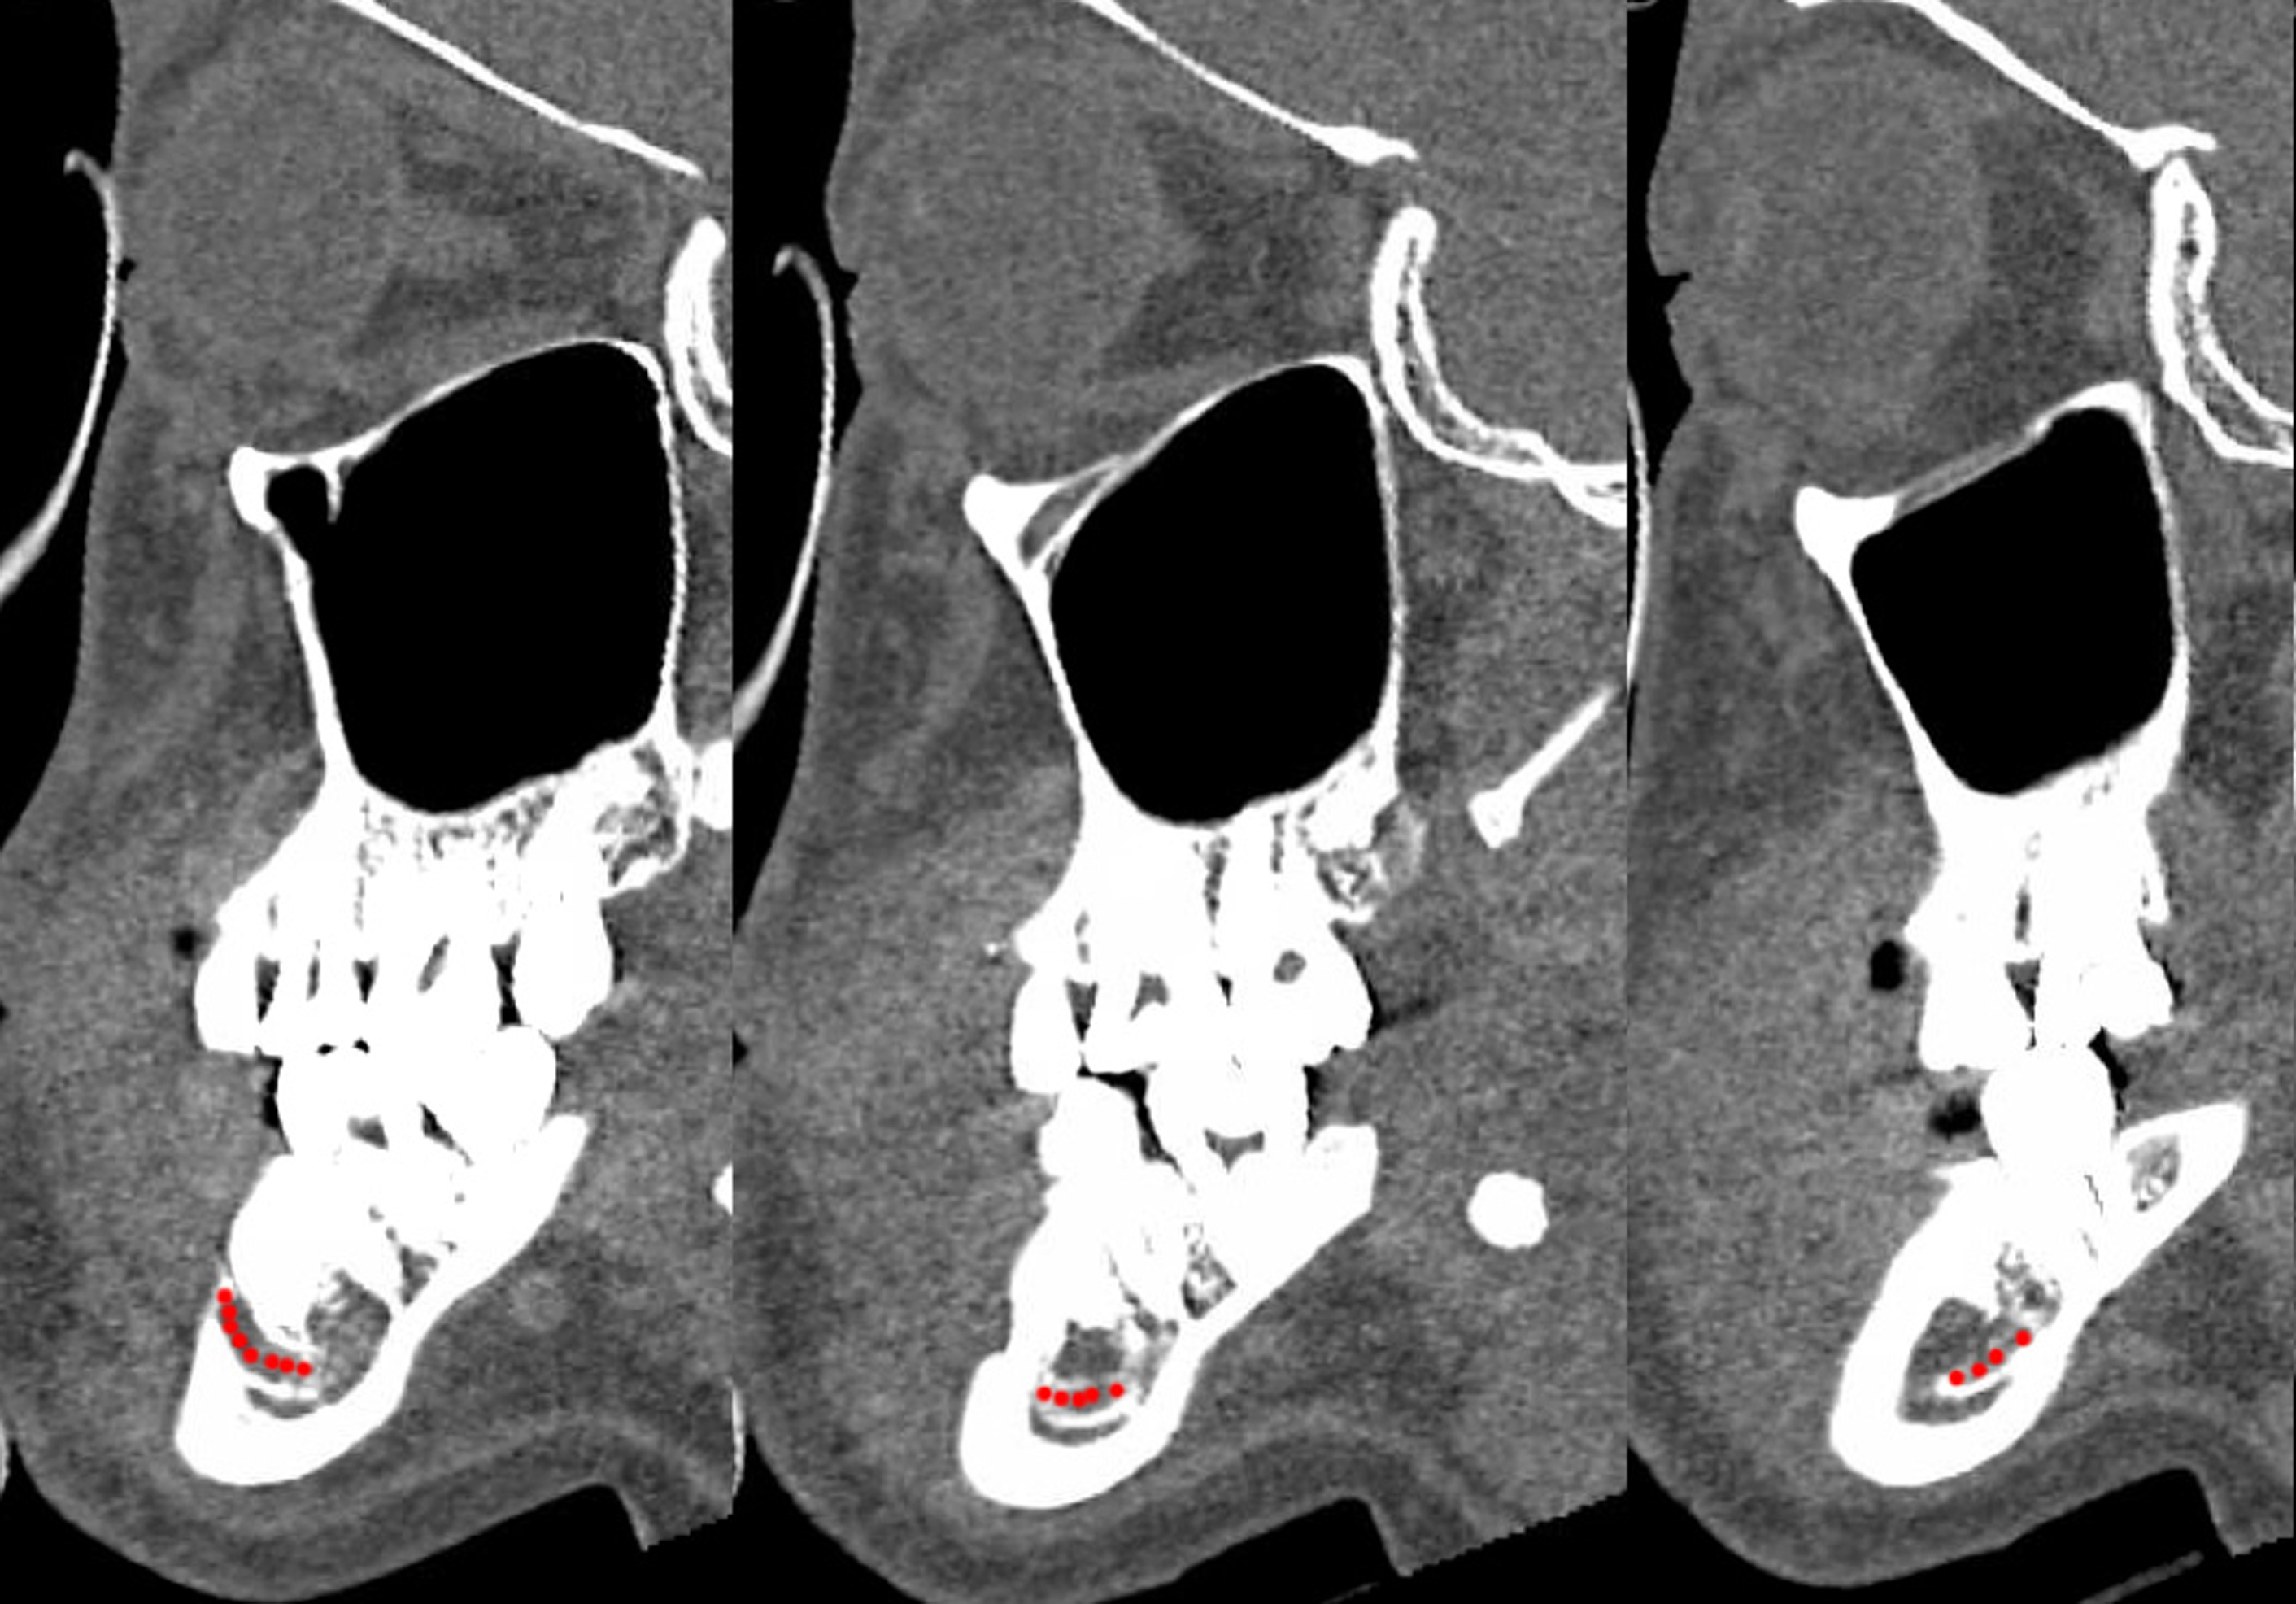

The mandibular body also contains the inferior alveolar nerve (IAN), a branch of the third division of the trigeminal nerve (V3). The IAN enters via the mandibular foramen on the lingual surface of the ramus and travels inferiorly and anteriorly within the bone, exiting via the mental foramen. The mental foramen is located at the level or just anterior to the second premolar ( Fig. 2 ). Just before exiting the mental foramen, the nerve will ascend superiorly. Thus, the level of the IAN as it runs through the mandibular body is inferior to the level of the mental foramen ( Fig. 3 ). The mental nerve divides into several branches innervating the chin, lower lip, and gingiva as it exists the mental foramen. In edentulous patients, the IAN position may shift superiorly as the dentoalveolar bone degenerates.